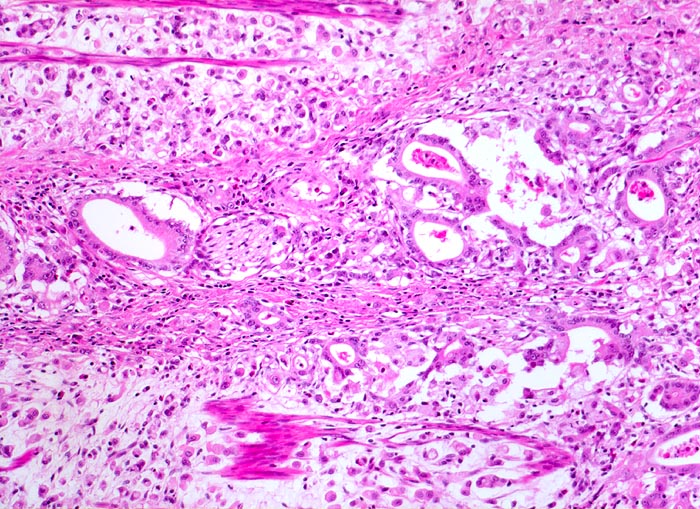

Die ersten beiden Typen entsprechen histologisch meist einem intestinalen Typ nach Lauren (> 1342). Diese Tumoren sind scharf begrenzt, bilden tubuläre oder papilläre Strukturen wie die Dickdarmkarzinome, sind meist assoziiert mit bekannten umweltbedingten Risikofaktoren und haben eine bessere Prognose.

Adenokarzinome können tubuläre, papilläre, muzinöse, siegelringzellige und undifferenzierte Anteile aufweisen, wobei die beiden letzteren besonders aggressive Tumoren darstellen.

• Nur vereinzelt Drüsenbildung.